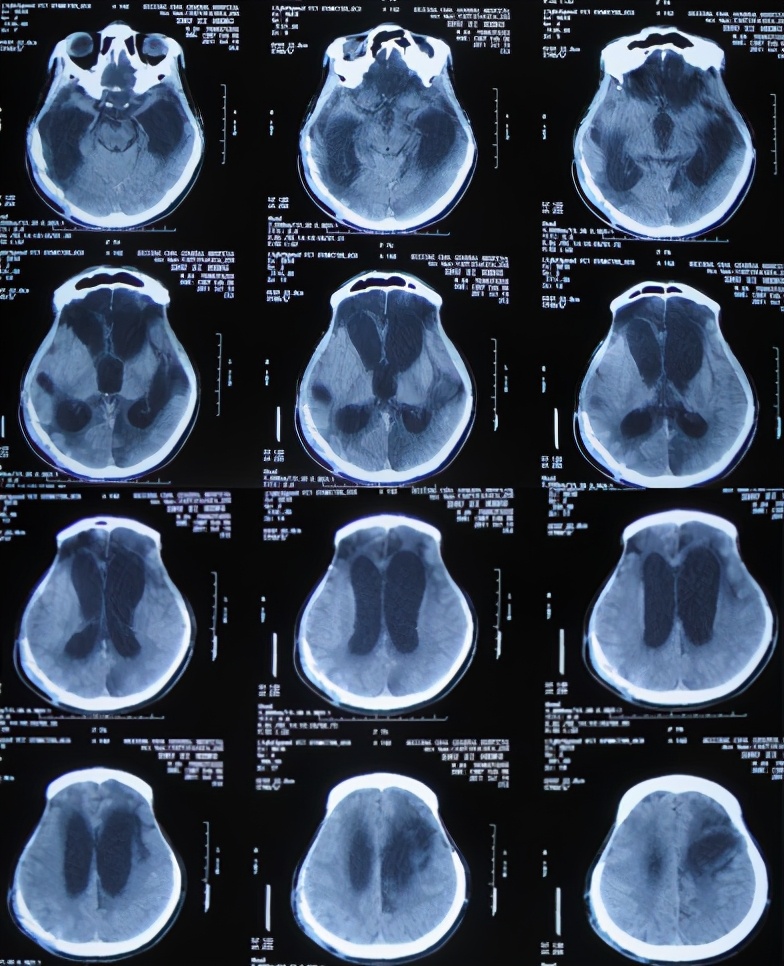

随后立即给予腰大池引流和抗感染治疗,27天后即2011年5月27日(干细胞移植治疗31天后即开颅术后132天),患者病情反而更加重,意识变差,仍间断发热;查头颅CT示仍脑积水和水肿变得更加严重( 图-5 ),因此不得不转入该院的重症监护室。

图-5: 2011年5月27日头颅CT

重症监护室治疗20天即2011年6月16日(干细胞移植治疗51天后即开颅术后152天),患者意识稍有好转,体温也变为正常;查头颅CT示脑积水仍未见改善( 图-6 ),所以转回普通病房。

图-6: 2011年6月16日头颅CT

开颅术后185天即2011年7月19日(干细胞移植治疗84天后),患者病情不见好转,反而更重:不能遵嘱活动,已不能简单言语,头颅CT示脑积水仍没有改善( 图-7 )。

图-7: 2011年7月19日头颅CT